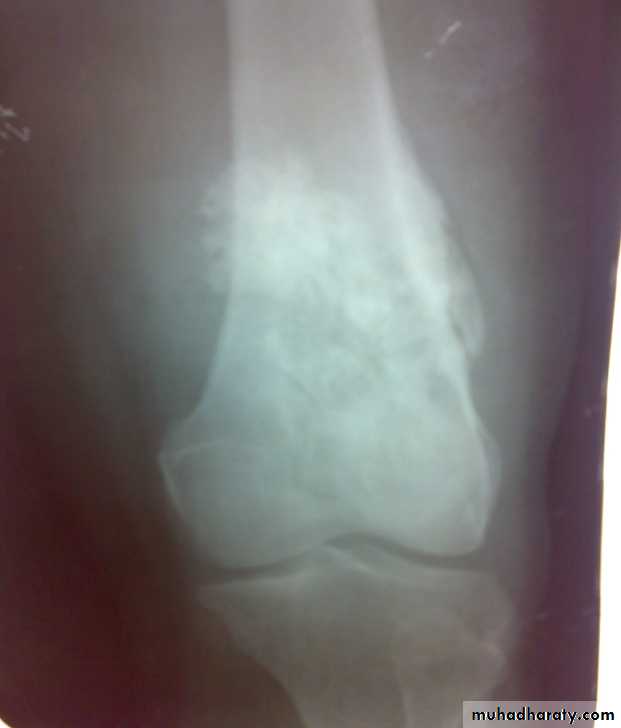

: X-ray are very variable but it show combination of bone destruction and bone formation.

The metaphysis show osteolytic and osteoblastic areas, the cortex is usually perforated and soft tissue shadow may be seen.

There is new bone formation in form of Codman's triangle at periphery of when cortex penetration cause periostium elevation and vertical streaks of calcification in the adjacent soft tissues called sunray appearance.